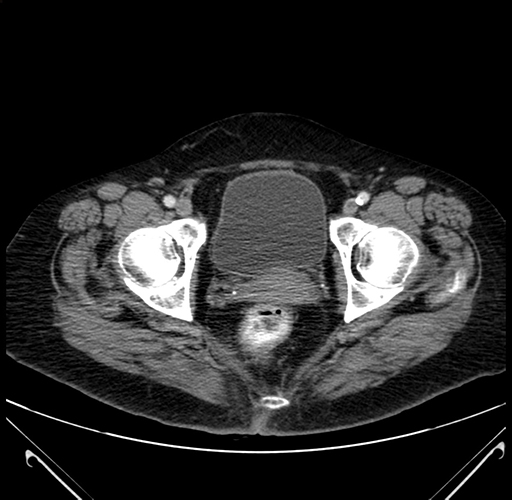

Pre-Chemo: Axial Venous

Axial Venous